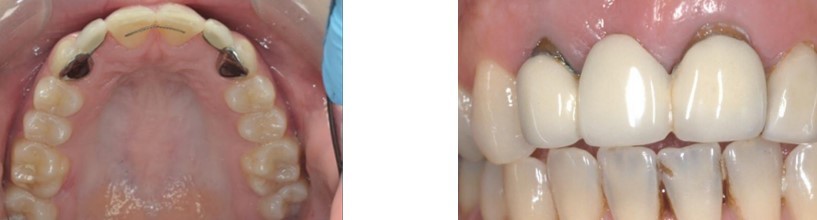

fixed-fixed bridge

This type of bridge has a retainer at each end with a pontic in the middle joined by rigid connectors.